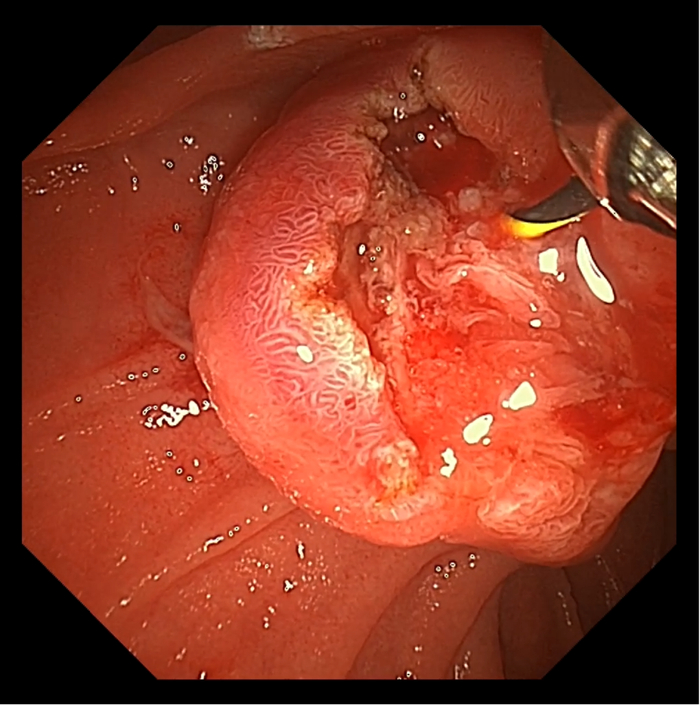

患者男,65岁。于十二指肠内侧找见主乳头,乳头呈鼻型,开口呈绒毛样。胆管狭窄导致反复超选导丝无法进入,后使用一次性粘膜切开刀,沿胆管方向行预切开,再次插管导丝进入胆管,注入少量造影剂,胆管显彰。

患者于三月后更换胆管支架,十二指肠镜应用操作如图所示:

术后,王雷教授表示道,澳华全新一代UHD-ED300V十二指肠镜在4K超高清内镜系统AQ-300的加持下,即使是面对高度复杂的ERCP手术也不在话下。

在高分辨率之下,可为医生提供更加清晰的观察条件,助力辨认十二指肠的异常病变、快速找到十二指肠乳头,利于医者更加精准迅速做出正确决策,为患者提供更安全、有效的治疗体验。